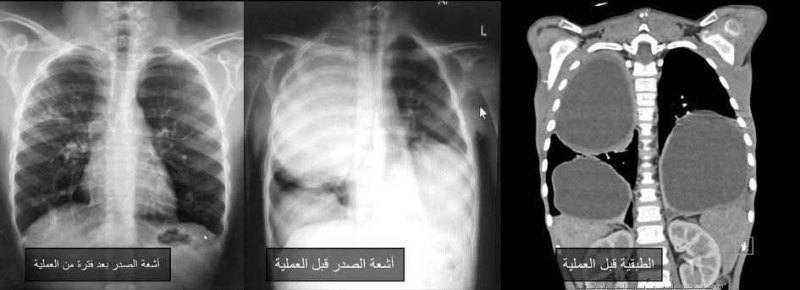

وبحسب بيان المستشفى، اليوم الأحد، تكمن ندرة الحالة في أن "الأكياس الكلابية" تصيب الكبد غالبا، وقد تنتقل لاحقا إلى الرئتين، بينما تعد إصابة الرئتين فقط، وبشكل متعدد وضخم في الجهتين، من الحالات النادرة جدا، وقد جرى اكتشاف الحالة دون أعراض واضحة من قبل استشاري أمراض التنفسية والصدرية لدى الأطفال، الدكتورة إيناس الزيادنة، وفريقها الطبي.

ونظرا لتعقيد الحالة وصعوبتها التخديرية والجراحية، تولى فريق التخدير بقيادة استشاري تخدير الأطفال الدكتور عمر عبابنة تقديم عناية تخديرية متقدمة، مكنت من إجراء عمليتين جراحيتين كبيرتين ومتتاليتين بأمان، فيما أجرى فريق جراحة الأطفال برئاسة استشاري جراحة الأطفال بالمنظار الدكتور رائد الطاهر العمليتين بنجاح كامل ودون مضاعفات، باستخدام المنظار الصدري بدلا من فتح الصدر الجراحي التقليدي.

وساهم استخدام المنظار والثقوب الجراحية الصغيرة في تسريع تعافي الطفل بعد العملية الأولى للرئة اليمنى، ما أتاح إجراء العملية الثانية للرئة اليسرى بعد نحو أسبوعين فقط، وبنفس التقنية، وقد تعافى الطفل بشكل تام، وغادر المستشفى خلال مدة قياسية، مع متابعة طبية استمرت لعدة أشهر أكدت عودته لممارسة حياته الطبيعية دون أي مضاعفات.